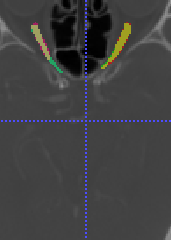

In Chapter 6, we propose an end-to-end, atlas-free 3D convolutional deep learning framework for fast and fully automated whole-volume HaN anatomy segmentation [115]. Our deep learning model, called AnatomyNet, segments OARs from head and neck CT images in an end-to-end fashion, receiving whole-volume HaN CT images as input and generating masks of all OARs of interest in one shot. AnatomyNet is built upon the popular 3D U-net architecture, but extends it in three important ways: 1) a new encoding scheme to allow auto-segmentation on whole-volume CT images instead of local patches or subsets of slices, 2) incorporating 3D squeeze-and-excitation residual blocks in encoding layers for better feature representation, and 3) a new loss function combining Dice scores and focal loss to facilitate the training of the neural model. These features are designed to address two main challenges in deep-learning-based HaN segmentation: a) segmenting small anatomies (i.e., optic chiasm and optic nerves) occupying only a few slices, and b) training with inconsistent data annotations with missing ground truth for some anatomical structures. We collect 261 HaN CT images to train AnatomyNet, and use MICCAI Head and Neck Auto Segmentation Challenge 2015 as a benchmark dataset to evaluate the performance of AnatomyNet. The objective is to segment nine anatomies: brain stem, chiasm, mandible, optic nerve left, optic nerve right, parotid gland left, parotid gland right, submandibular gland left, and submandibular gland right. Compared to previous state-of-the-art results from the MICCAI 2015 competition, AnatomyNet increases Dice similarity coefficient by 3.3% on average. AnatomyNet takes about 0.12 seconds to fully segment a head and neck CT image of dimension , significantly faster than previous methods. In addition, the model is able to process whole-volume CT images and delineate all OARs in one pass, requiring little pre- or post-processing. We demonstrate that our proposed model can improve segmentation accuracy and simplify the auto-segmentation pipeline. These contributions are released as an open-source software package called AnatomyNet, which is publicly available555https://github.com/wentaozhu/AnatomyNet-for-anatomical-segmentation. Portions of this chapter were published as part of [115].

- [121] W. Zhu and X. Xie. Adversarial deep structural networks for mammographic mass segmentation. arXiv:1612.05970, 2016.